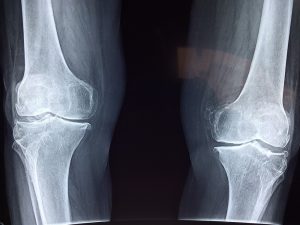

Hvornår har man brug for en røntgenundersøgelse?